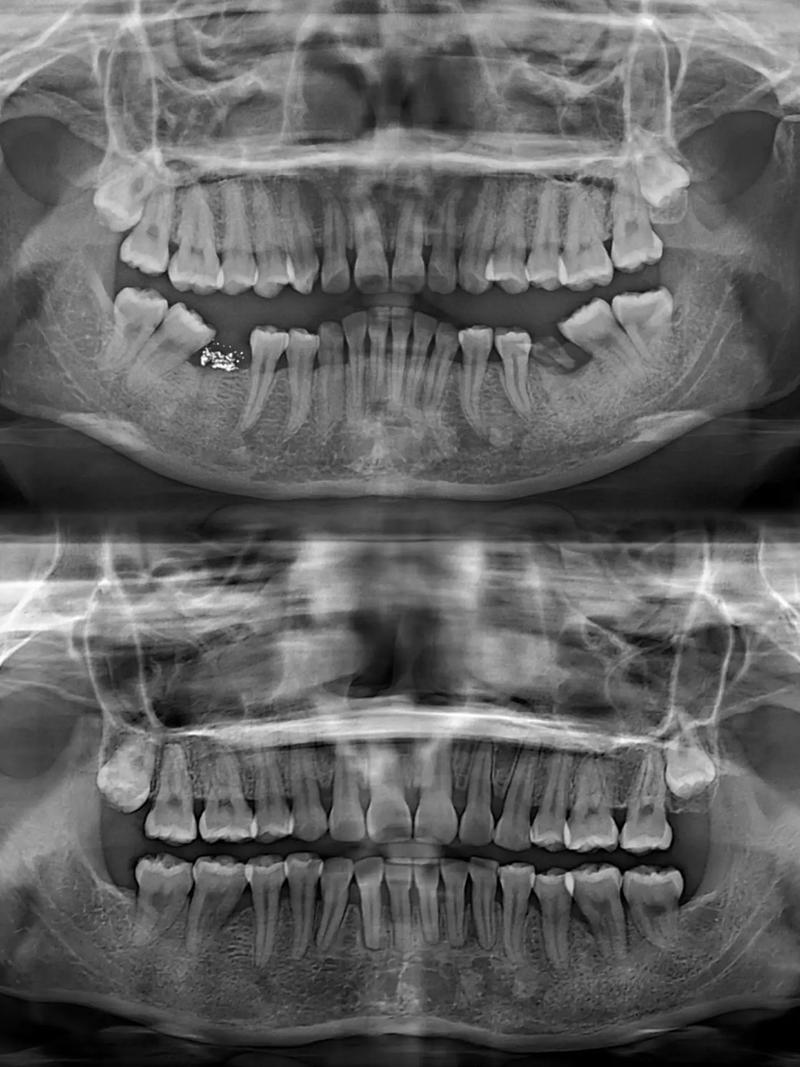

现代牙套矫正技术已高度成熟,包括传统金属托槽矫正、陶瓷半隐形矫正、隐形无托槽矫正(如隐形牙套)、舌侧矫正等多种方式,均基于相同的生物力学原理,但通过材料、设计的优化,提升了舒适度、美观度和适配性,专业正畸医生会通过X光片、口腔模型、数字化口扫等手段,分析患者的牙齿排列、颌骨发育、面部比例等情况,制定个性化的矫正方案,确保矫正过程安全、可控。

Q2:成年后矫正效果比青少年差吗?需要拔牙吗?

A:成年后矫正效果与青少年相当,只要牙周健康即可进行,是否拔牙取决于错颌程度和空间需求,并非所有矫正都需要拔牙,医生会通过模型测量、X光片分析等手段,判断是否需要拔牙(通常拔除前磨牙以提供排齐空间),并尽量选择对功能影响小的牙齿。